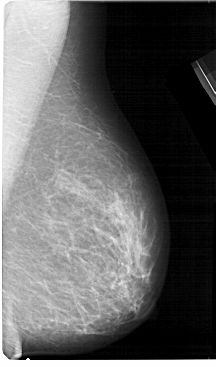

A_1323_1.RIGHT_MLO

RIGHT_MLO LINES 5491 PIXELS_PER_LINE 3226 BITS_PER_PIXEL 12 RESOLUTION 43.5 NON_OVERLAY